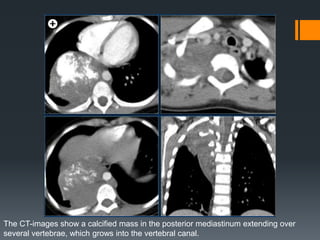

The CT-images show a calcified mass in the posterior mediastinum extending over

several vertebrae, which grows into the vertebral canal.